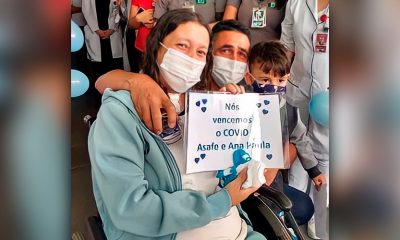

Ela permaneceu quase um mês intubada e necessitou de uma traqueostomia

Mulher passou por cesariana de emergência enquanto lutava pela vida, em tratamento contra coronavírus